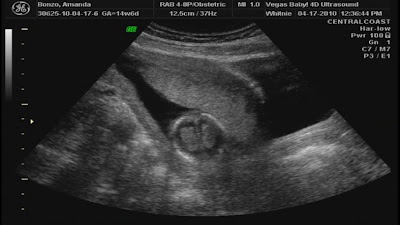

Earlier this week we went in for a gender ultrasound. Found out it's a girl! We are going to have a daughter! :) Check out the previous post for pictures of this beautiful lady!

What our baby GIRL has been up to this week:

She is about 4 inches long and weighs about 2 1/2 ounces. She is busy breathing in the amniotic fluid which is helping develop her lungs and upper respiratory tract. Her arms and legs are growing longer and she can now move all of her joints and limbs. Even though her eyes are sitll fused shut, she can sense light through the belly and move away from it.